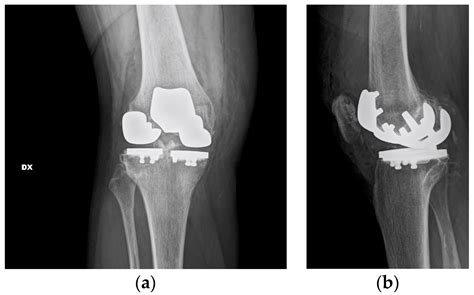

When non-surgical treatments are no longer effective, surgical intervention may be necessary. Surgical options for tricompartmental degenerative arthrosis include:

• Partial Knee Replacement: Replacing only the damaged compartments of the knee while preserving the healthy parts.

• Total Knee Replacement: Replacing all three compartments of the knee with artificial components to restore function and relieve pain.

📝 Note: The choice of surgical procedure depends on the severity of the condition, the patient's overall health, and their specific needs and goals.